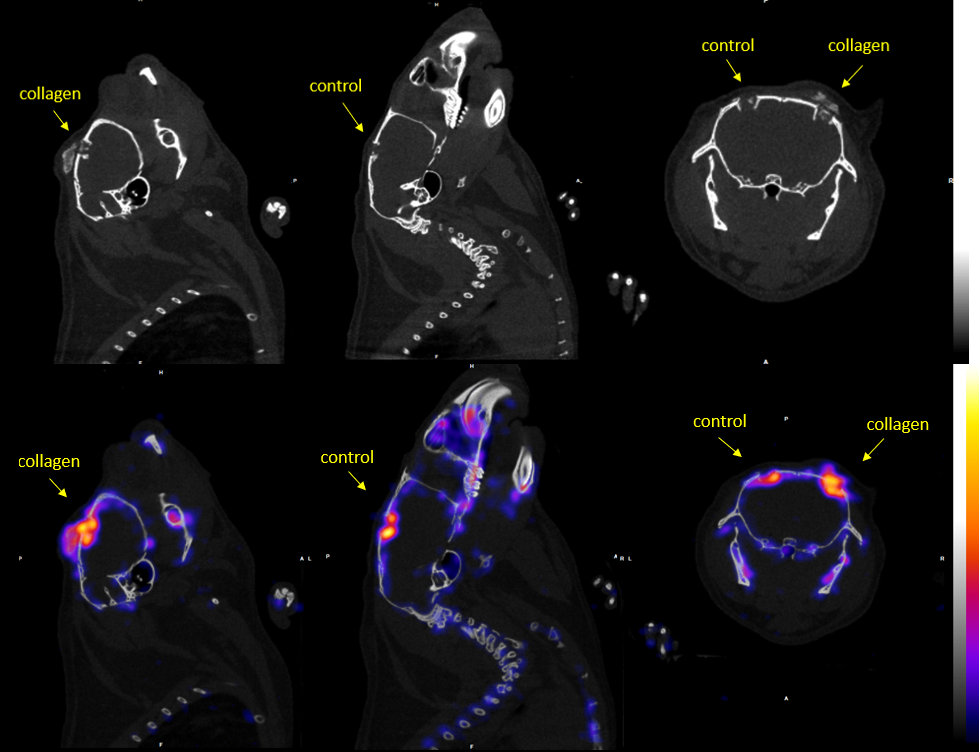

The main task of this WP, included the creation of an animal defect model and the dispersion of the prepared collagen material on the small animal bone injury models (mice) to be monitored through SPECT and CT imaging. The procedure to also incorporate the magnetic nanoparticles (MNPs) as a contrast agent was followed and MRI tests were performed to validate the image contrast induction.

Results proved the creation and establishment of a complete imaging platform that can non-invasively monitor the evaluation of new bone graphs, in bone formation schemes, through multi-modal imaging. The complementary information gathered through SPECT, CT and MRI imaging was demonstrated and exploited towards the creation of the imaging platform.

Experimental results of SPECT/CT imaging of bone tissue regeneration